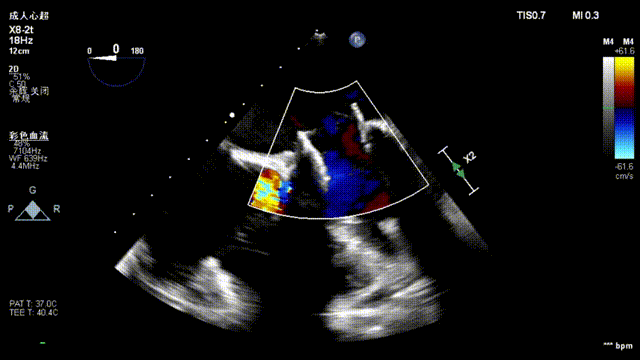

浙江大学医学院附属第一医院袁帅教授分享了他在经心尖TAVI手术中应用经食道超声心动图检查TEE的经验和技巧。袁帅教授指出,灵活应用TEE可以对术前经胸超声进行补充,辅助术中造影,术后快速评估手术效果,及时发现潜在的手术并发症。通过对TEE的全面应用,术者可以更加准确地诊断和评估患者的病情,为手术提供更深入的支持。此外,袁帅教授还分享了一些在TAVI手术中常用的TEE投射切面以及其他使用技巧。借助TEE技术,术者可以更好地监测植入瓣膜的位置和角度,并及时采取调整手段,确保手术效果和安全性。